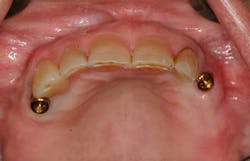

After uncovering the implants, Locator abutments were torqued to 30 Ncm (figure 1). Parallel posts were seated on the abutments, and complete seating of the original RPD was confirmed (figure 2). It was planned to remove the existing metal clasps at sites of Nos. 5 and 11, so they were removed at this time to prevent interference with the parallel posts. Clasps can also be removed at the lab if desired. A small amount of PVS adhesive was placed on the intaglio surface prior to seating the RPD.